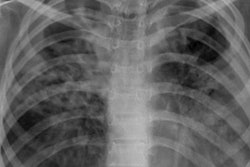

Lateral chest radiographs help to detect clinically suspected pulmonary TB, particularly in children. A number of studies in the literature have showed the benefit of lateral chest x-rays in, for example, identifying mediastinal or hilar lymphadenopathy and for providing information on the thoracic cage, pleura, lungs, pericardium, heart, mediastinum, and upper abdomen, according to the researchers.

A Bitwise-AND ensemble generated using the heatmaps produced by the top two performing models, VGG-16 and DenseNet-121 models. (A) and (E) Sample test lateral chest x-rays with expert ground truth annotations (shown in red bounding box); (B) and (F) heatmaps produced by the VGG-16 model; (C) and (G) heatmaps produced by the DenseNet-121 model, and (D) and (H) mask resulting from the Bitwise-AND operation of the heatmaps produced by the VGG-16 and DenseNet-121 models. Image and caption courtesy of Sivaramakrishnan Rajaraman, PhD, et al and Frontiers in Genomics through Creative Commons Attribution 4.0 International License.Delving further into the results from the algorithms, the researchers used class-selective maps to review the decisions of the CNNs and attention maps to review the results of the ViTs. These results were then combined to highlight the regions of the image that contributed to the algorithms' final output.